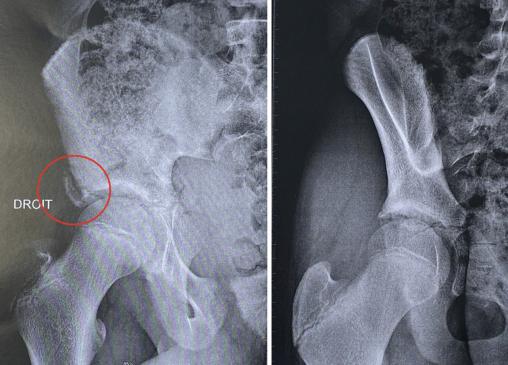

Fracture-avulsion de l’épine iliaque antéro-inférieure